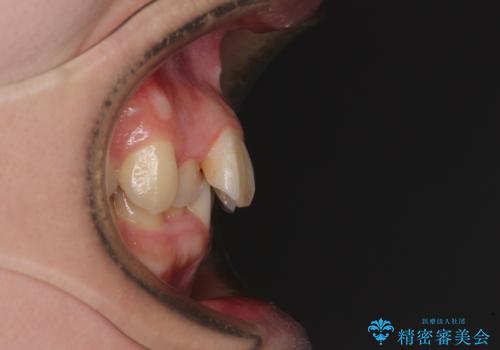

上下の前歯にデコボコがあり、更にはディープバイトにより下顎前歯の大半が隠れている状態でした。

上顎左右第一小臼歯の2本を抜歯し、ワイヤー装置を使用して咬み合わせ高さを改善しながら、歯列を整えて行くこととしました。